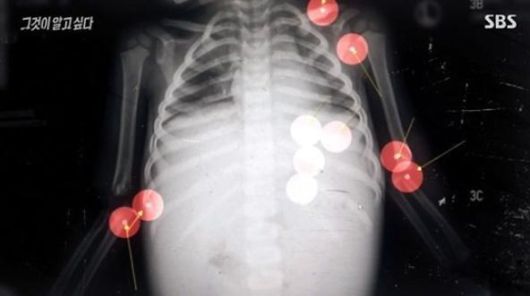

검찰은 정인이의 사인을 등 쪽에 가해진 강한 충격으로 인한 복부 손상으로 봤지만 어떤 방법으로 충격이 가해졌는지가 밝혀지지 않아 살인이 아닌 아동학대치사 혐의만 적용해 재판에 넘긴 상태다.

임현택 소아청소년과의사회장은 중앙일보와의 인터뷰에서 "정인이 정도의 손상은 양모가 손바닥으로 찰싹 때린 것이 아니라 주먹으로 때린 거다. 상복부의 명치와 갈비뼈 끝을 만져 내려가 보면 보호되는 장기가 있다. 갈비뼈로 폐와 간이 보호되는데, 췌장은 노출되는 위치에 있다. 그래서 상복부인데 갈비뼈 아랫부분을 정인이가 강하게 맞은 것으로 추측된다"고 설명했다.

이어 췌장 절단에 대해서 임 회장은 "아이가 누운 상태에서 충격을 가하고 췌장이 찌그러질 정도면 아랫집에서도 굉장히 큰 소리가 들릴 수 있다. 국립과학수사연구원 감정에 의하면 사망 수일 전에 손상이 이미 있었고, 그 부분이 아물고 있었단 소견도 있었다. 사망한 날에는 '죽어봐라' 하고 칠 정도의 물리력을 가한 것으로 보인다"고 밝혔다.

특히 췌장은 보행자가 차에 부딪쳤을 때의 충격, 황소의 머리에 부딪힐 정도의 충격이 있어야 절단된다고 설명했다.